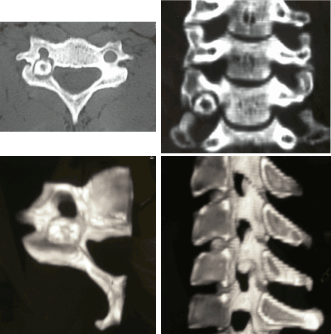

Figure 3 (a, b, c, d). CT examination showed an oval lesion surrounded by an area of sclerosis on the right articular process of C6 which formed the medial wall of the right vertebral artery foramen.